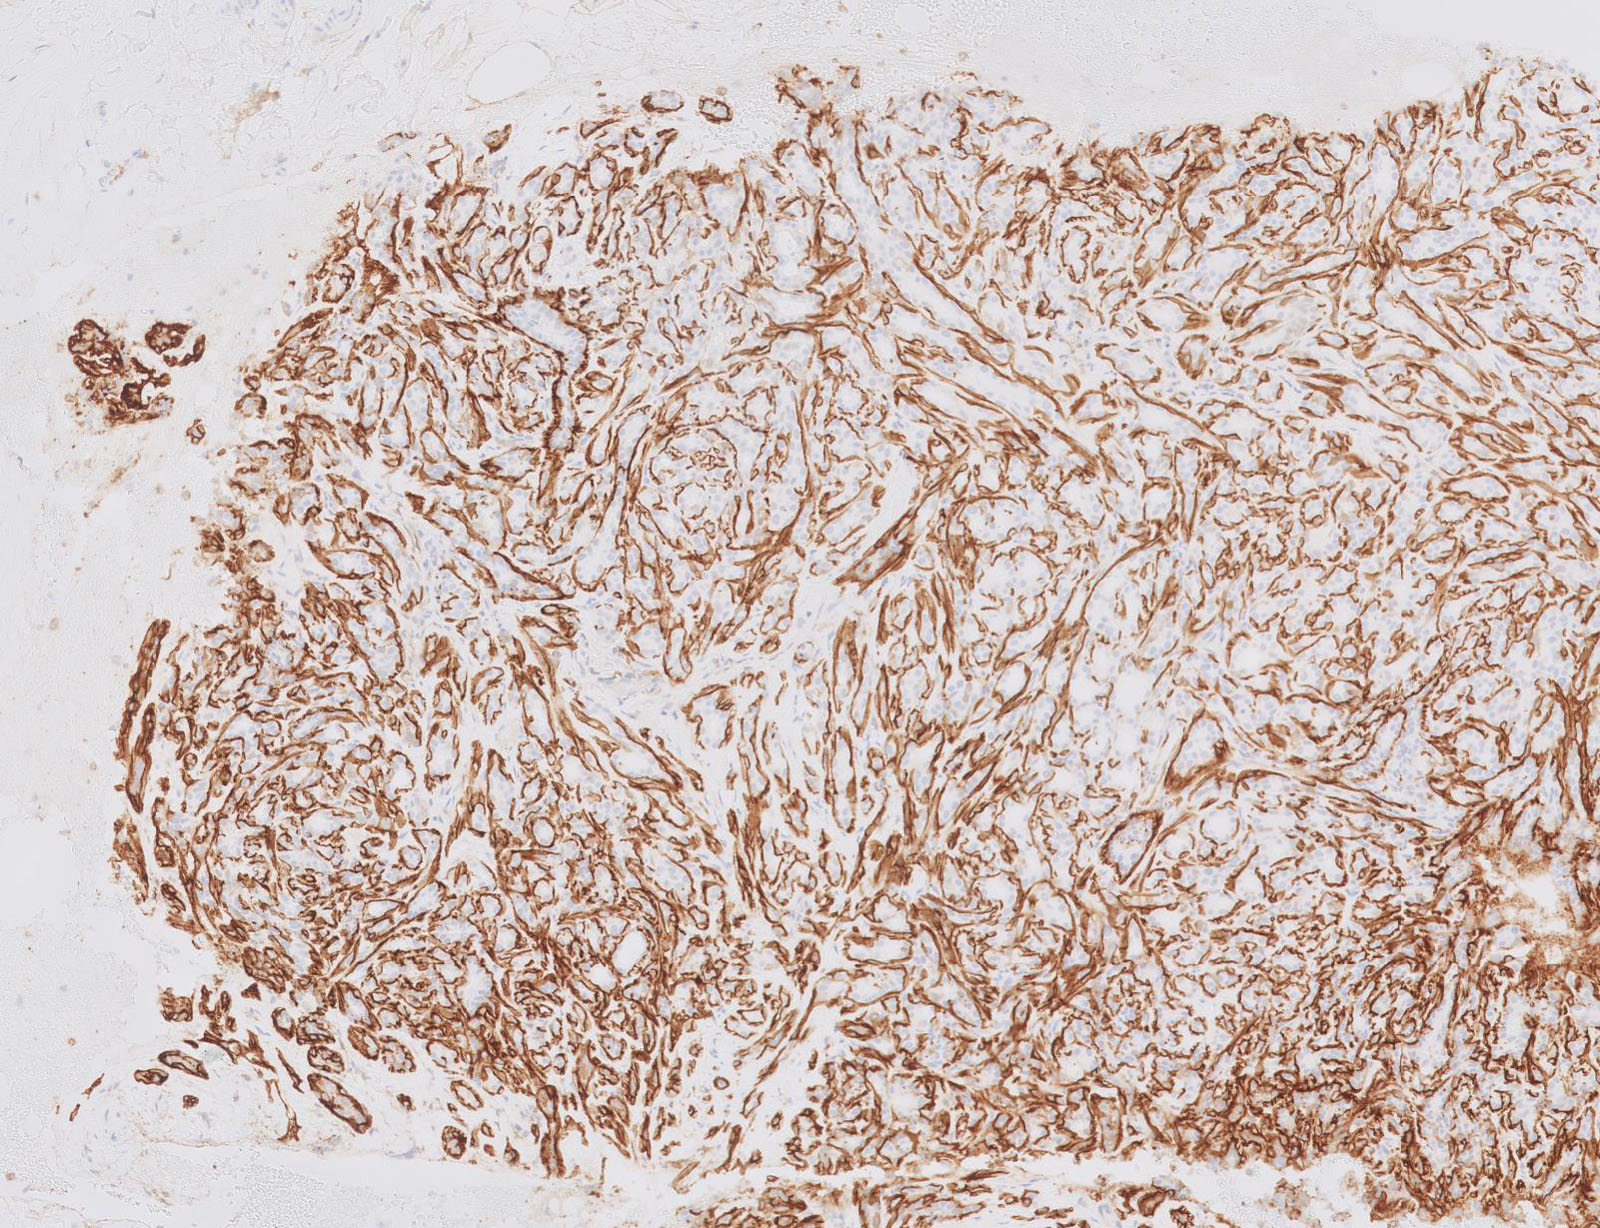

- Lined by an inner layer of luminal epithelial cells and an outer layer of myoepithelial cells

- Lined by an inner layer of luminal epithelial cells and an outer layer of myoepithelial cells

Microscopic (histologic) images

Contributed by Joshua J.X. Li, M.B.Ch.B. and Gary M. Tse, M.B.B.S.

Positive stains